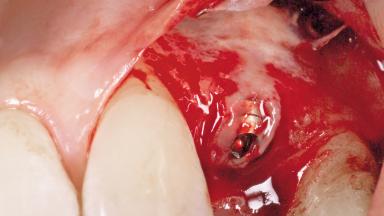

A 51-year-old female patient presented with a chief complaint of occlusal pain at tooth 24 and had been referred to our clinic for consultation and treatment. The patient had no history of any systemic disorder that may have affected the treatment outcome, and she was a non-smoker. Tooth 24 had been endodontically treated and restored with a crown at another clinic due to caries ten years before. The pre-treatment radiograph revealed a root fracture of tooth 24 with significant bone resorption. The pocket probing depth was 8 mm. The tooth had to be extracted. During the minimally traumatic extraction of tooth 24, a dehiscence was found on the buccal wall of the extraction socket. In response to the patient’s wish for a comprehensive treatment of the entire jaw,a suitable treatment plan was developed.